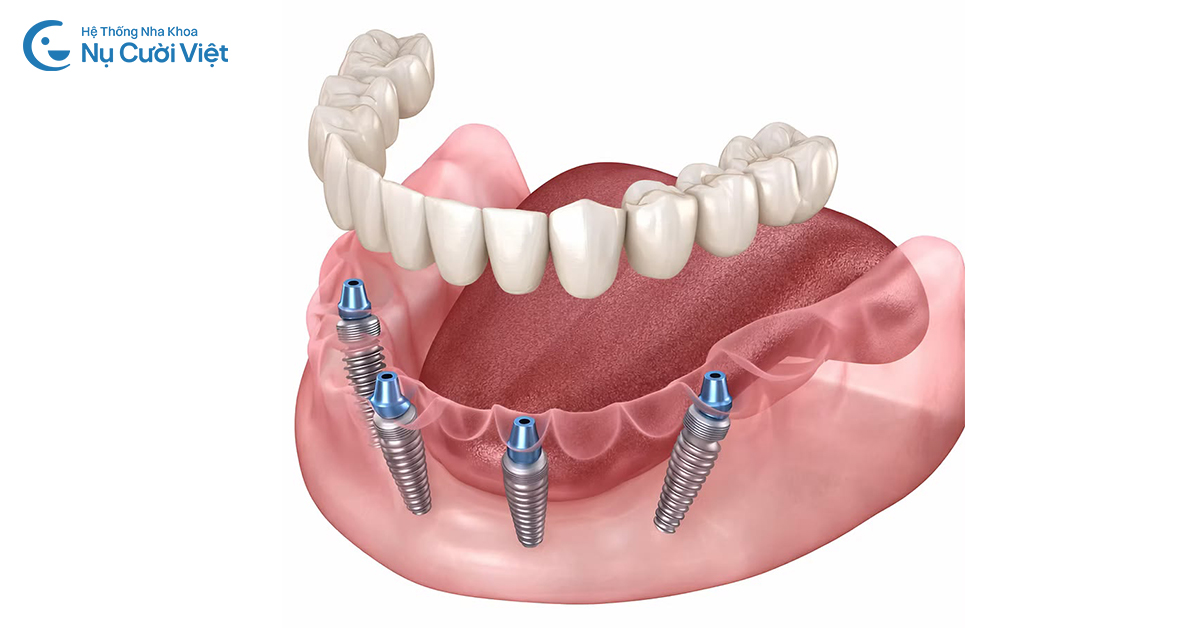

Cấy ghép Implant toàn hàm All-on-4 là kỹ thuật phục hình răng hiện đại, sử dụng chỉ 4 trụ Implant bằng Titanium sinh học để nâng đỡ toàn bộ hàm răng giả gồm 12-14 răng sứ phía trên. Phương pháp Implant toàn hàm này được thiết kế nhằm mang lại giải pháp hiệu quả cho những người mất nhiều răng hoặc mất toàn bộ răng trong một hàm.

Điểm đặc biệt của kỹ thuật này nằm ở sơ đồ đặt trụ: 2 trụ thẳng ở vị trí răng cửa và 2 trụ đặt nghiêng một góc lên đến 45 độ ở vùng răng hàm. Cấu trúc này tạo ra một "điểm tựa" vững chắc, tận dụng tối đa những vùng xương hàm còn tốt, giúp phục hồi chức năng ăn nhai và thẩm mỹ đạt đến 95% so với răng thật nhưng lại cực kỳ tối ưu về mặt chi phí. Hiệu quả cho người mất răng toàn hàm, thiếu xương ở vùng sau răng.